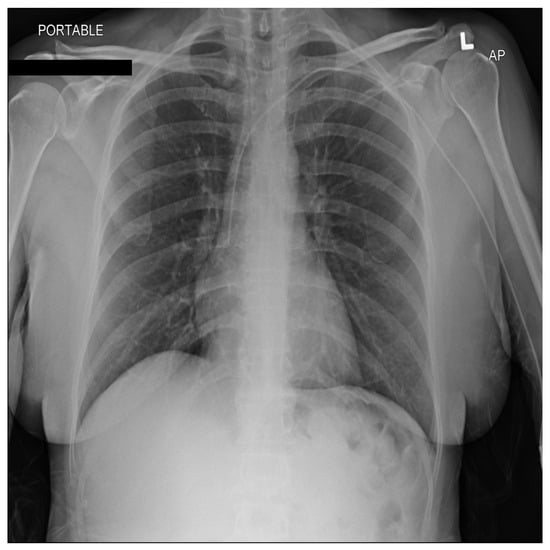

From a visual perspective, as illustrated in the comparison images above, both the RSCM as in Figure 1 and NIH as in Figure 2 datasets exhibit comparable quality in terms of resolution, clarity, and diagnostic relevance. This similarity ensures that image quality does not introduce any significant bias or variation.